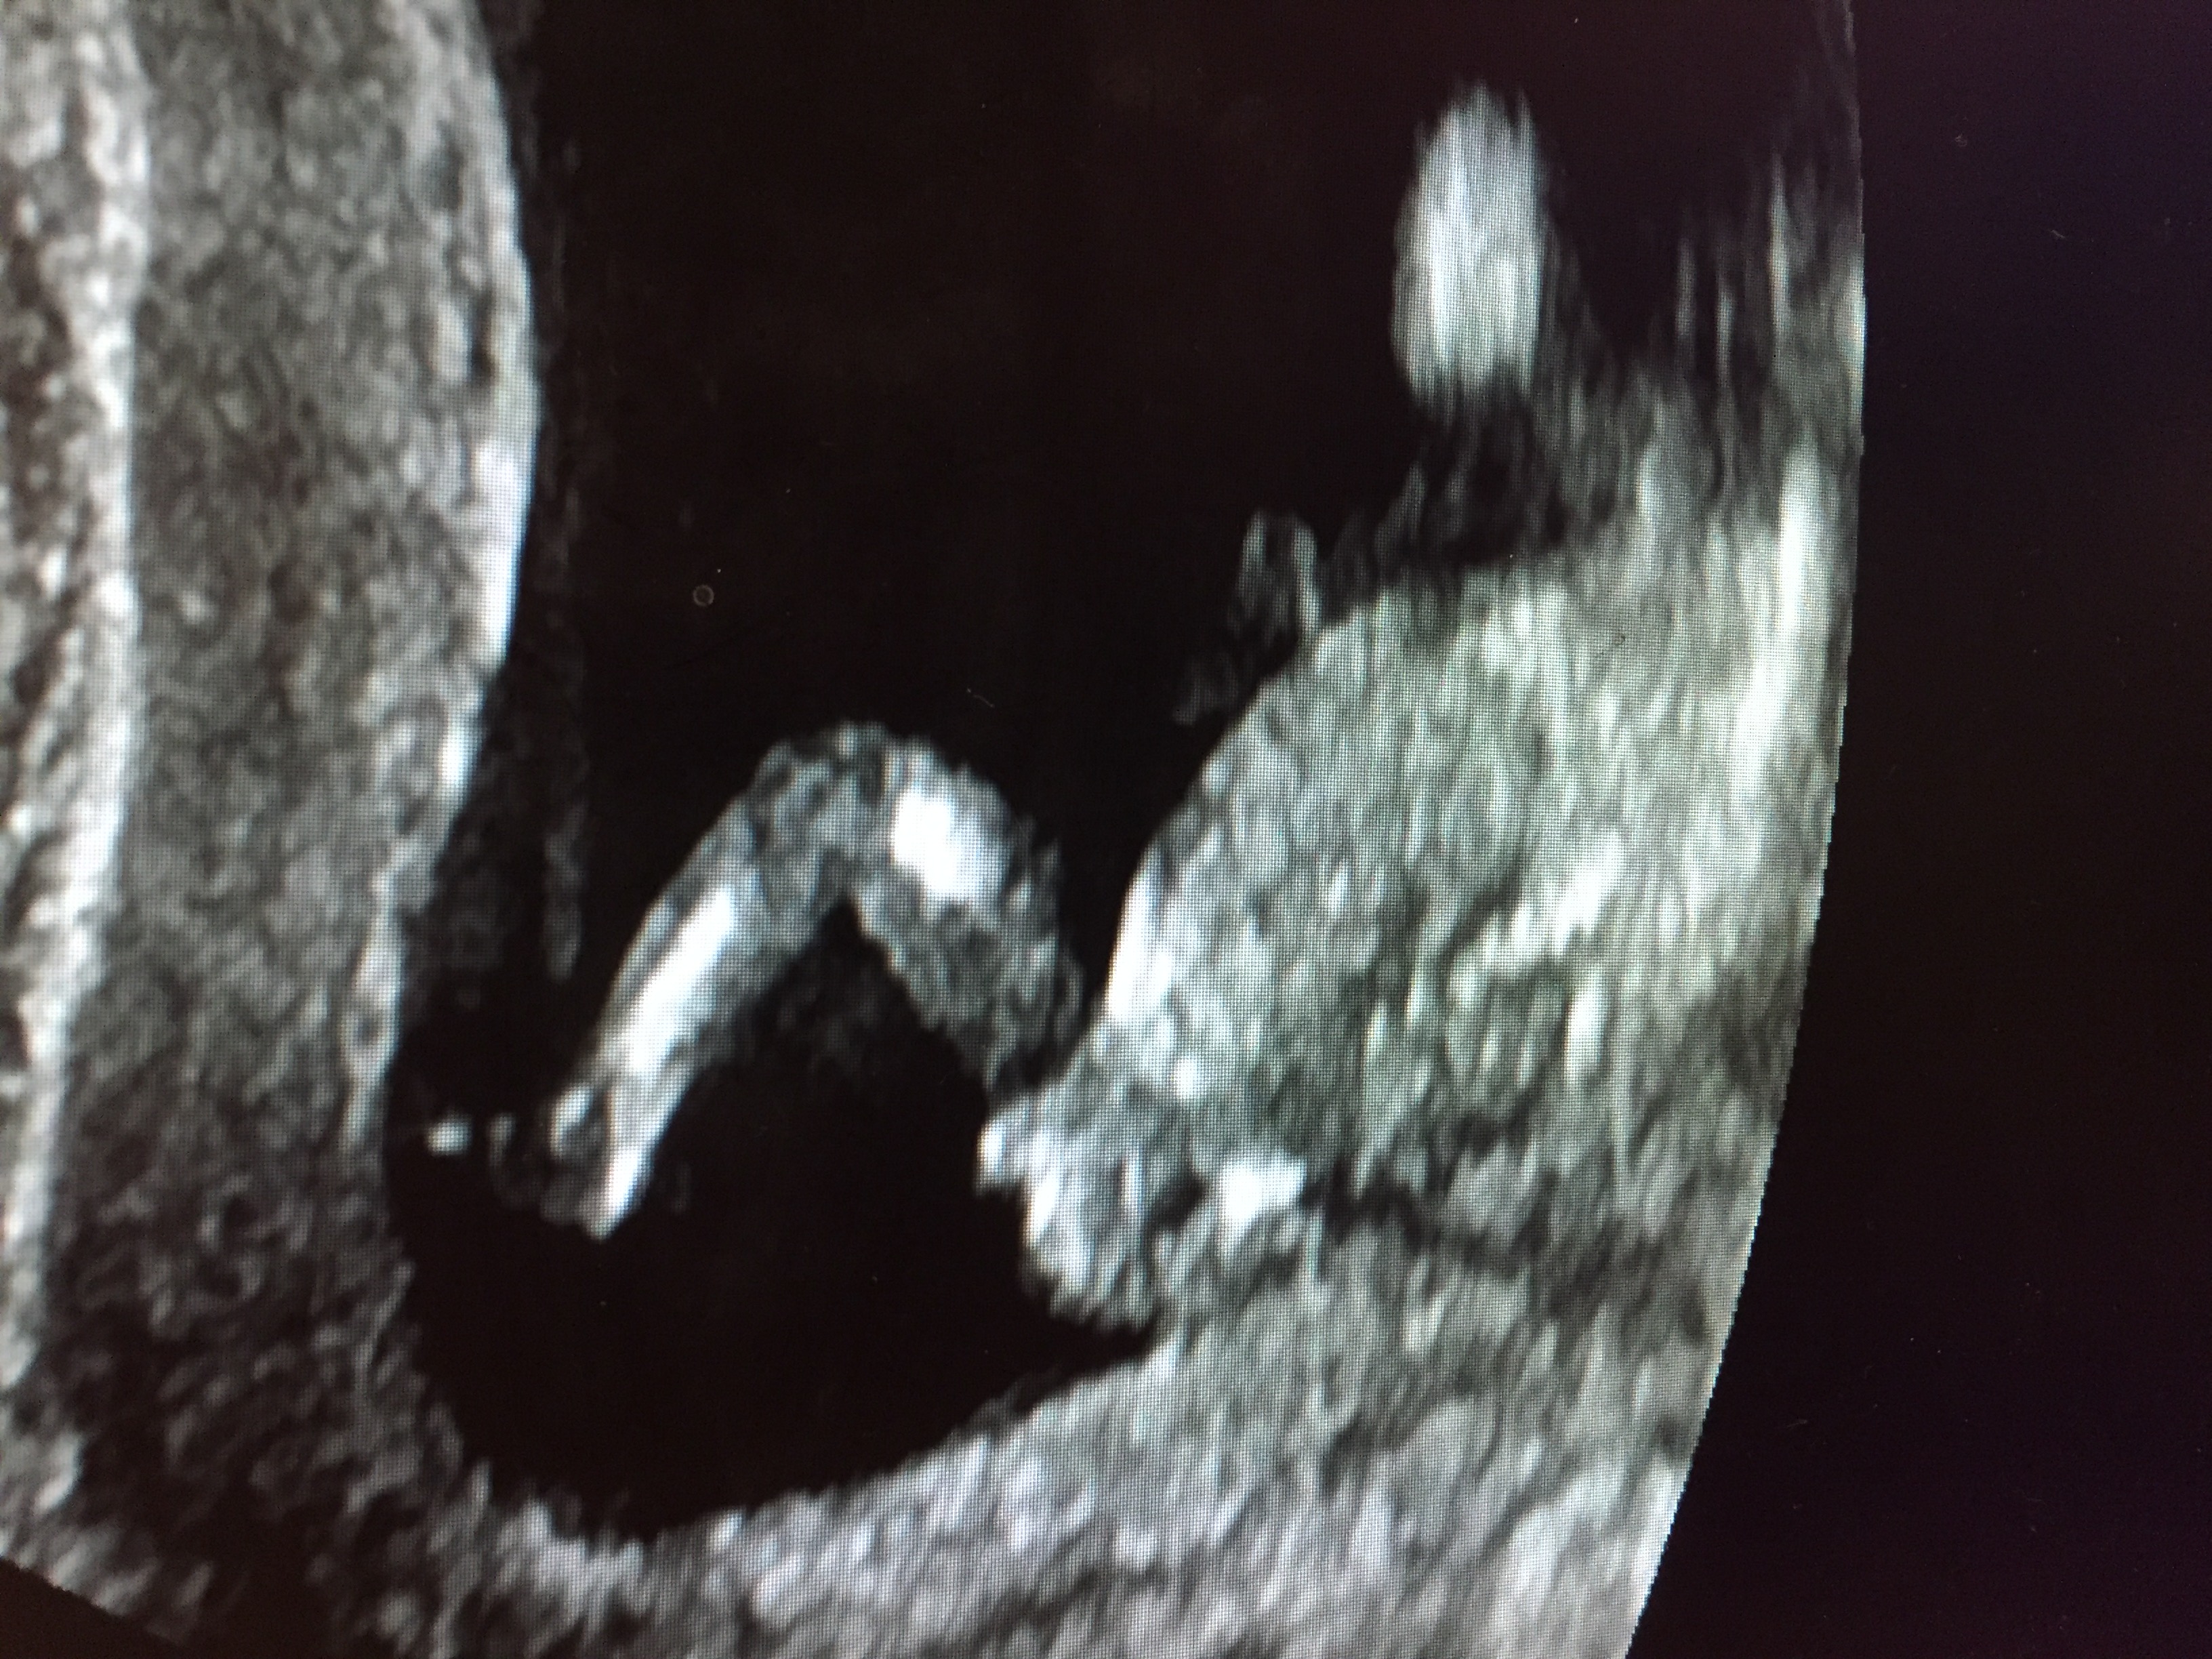

Attachment 37644Posting for a friend who is 13 weeks and six days by ultrasound. What are your thoughts?!

Boy

Looks like a boy

Boy [emoji170]